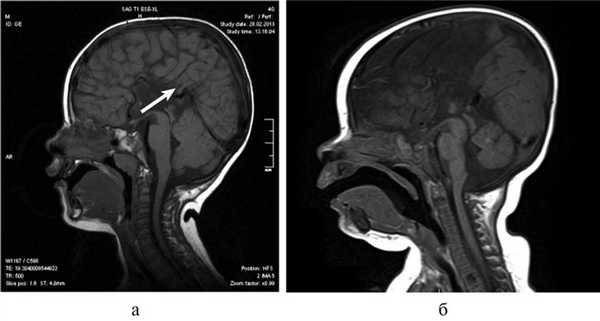

Рис. 3. МРТ головного мозга (сагиттальная проекция) больной С., 7 лет. АМТ (стрелка).

Важной находкой при АМТ на МРТ является параллельная ориентация тел боковых желудочков по отношению друг к другу (рис. 4, а), расширенные фронтальные отделы желудочков, так называемый «симптом ухвата».

Рис. 4. МРТ головного мозга больной К., 4 года. АМТ. Аксиальная проекция: а — аномальная параллельная ориентация тел боковых желудочков по отношению друг к другу (стрелка); б — фронтальное сечение: деформация передних и задних рогов боковых желудочков, своеобразный U-образный характер фронтальных отделов боковых желудочков (стрелка).

При МРТ мы обращали внимание также на описанное в литературе [12] изолированное расширение задних рогов — кольпоцефалию, обусловленную гипоплазией ассоциативных трактов белого вещества затылочных долей. Диагностический ряд на МРТ дополняют отсутствие нормально сформированных перикаллезных извилин (рис. 5, а) и радиальная центростремительная позиция борозд медиальной поверхности теменной доли (рис. 5, б).

Рис. 5. МРТ головного мозга больного А., 3 года. АМТ. а — сагиттальная проекция. Отсутствие нормально сформированных перикаллезных извилин (стрелка), б — высокое положение III желудочка, радиальная центростремительная направленность борозд медиальной поверхности теменных долей.